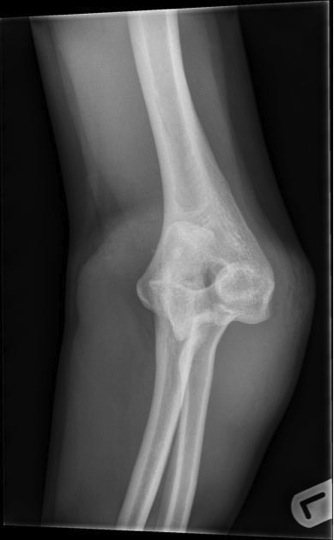

Elbow Dislocation